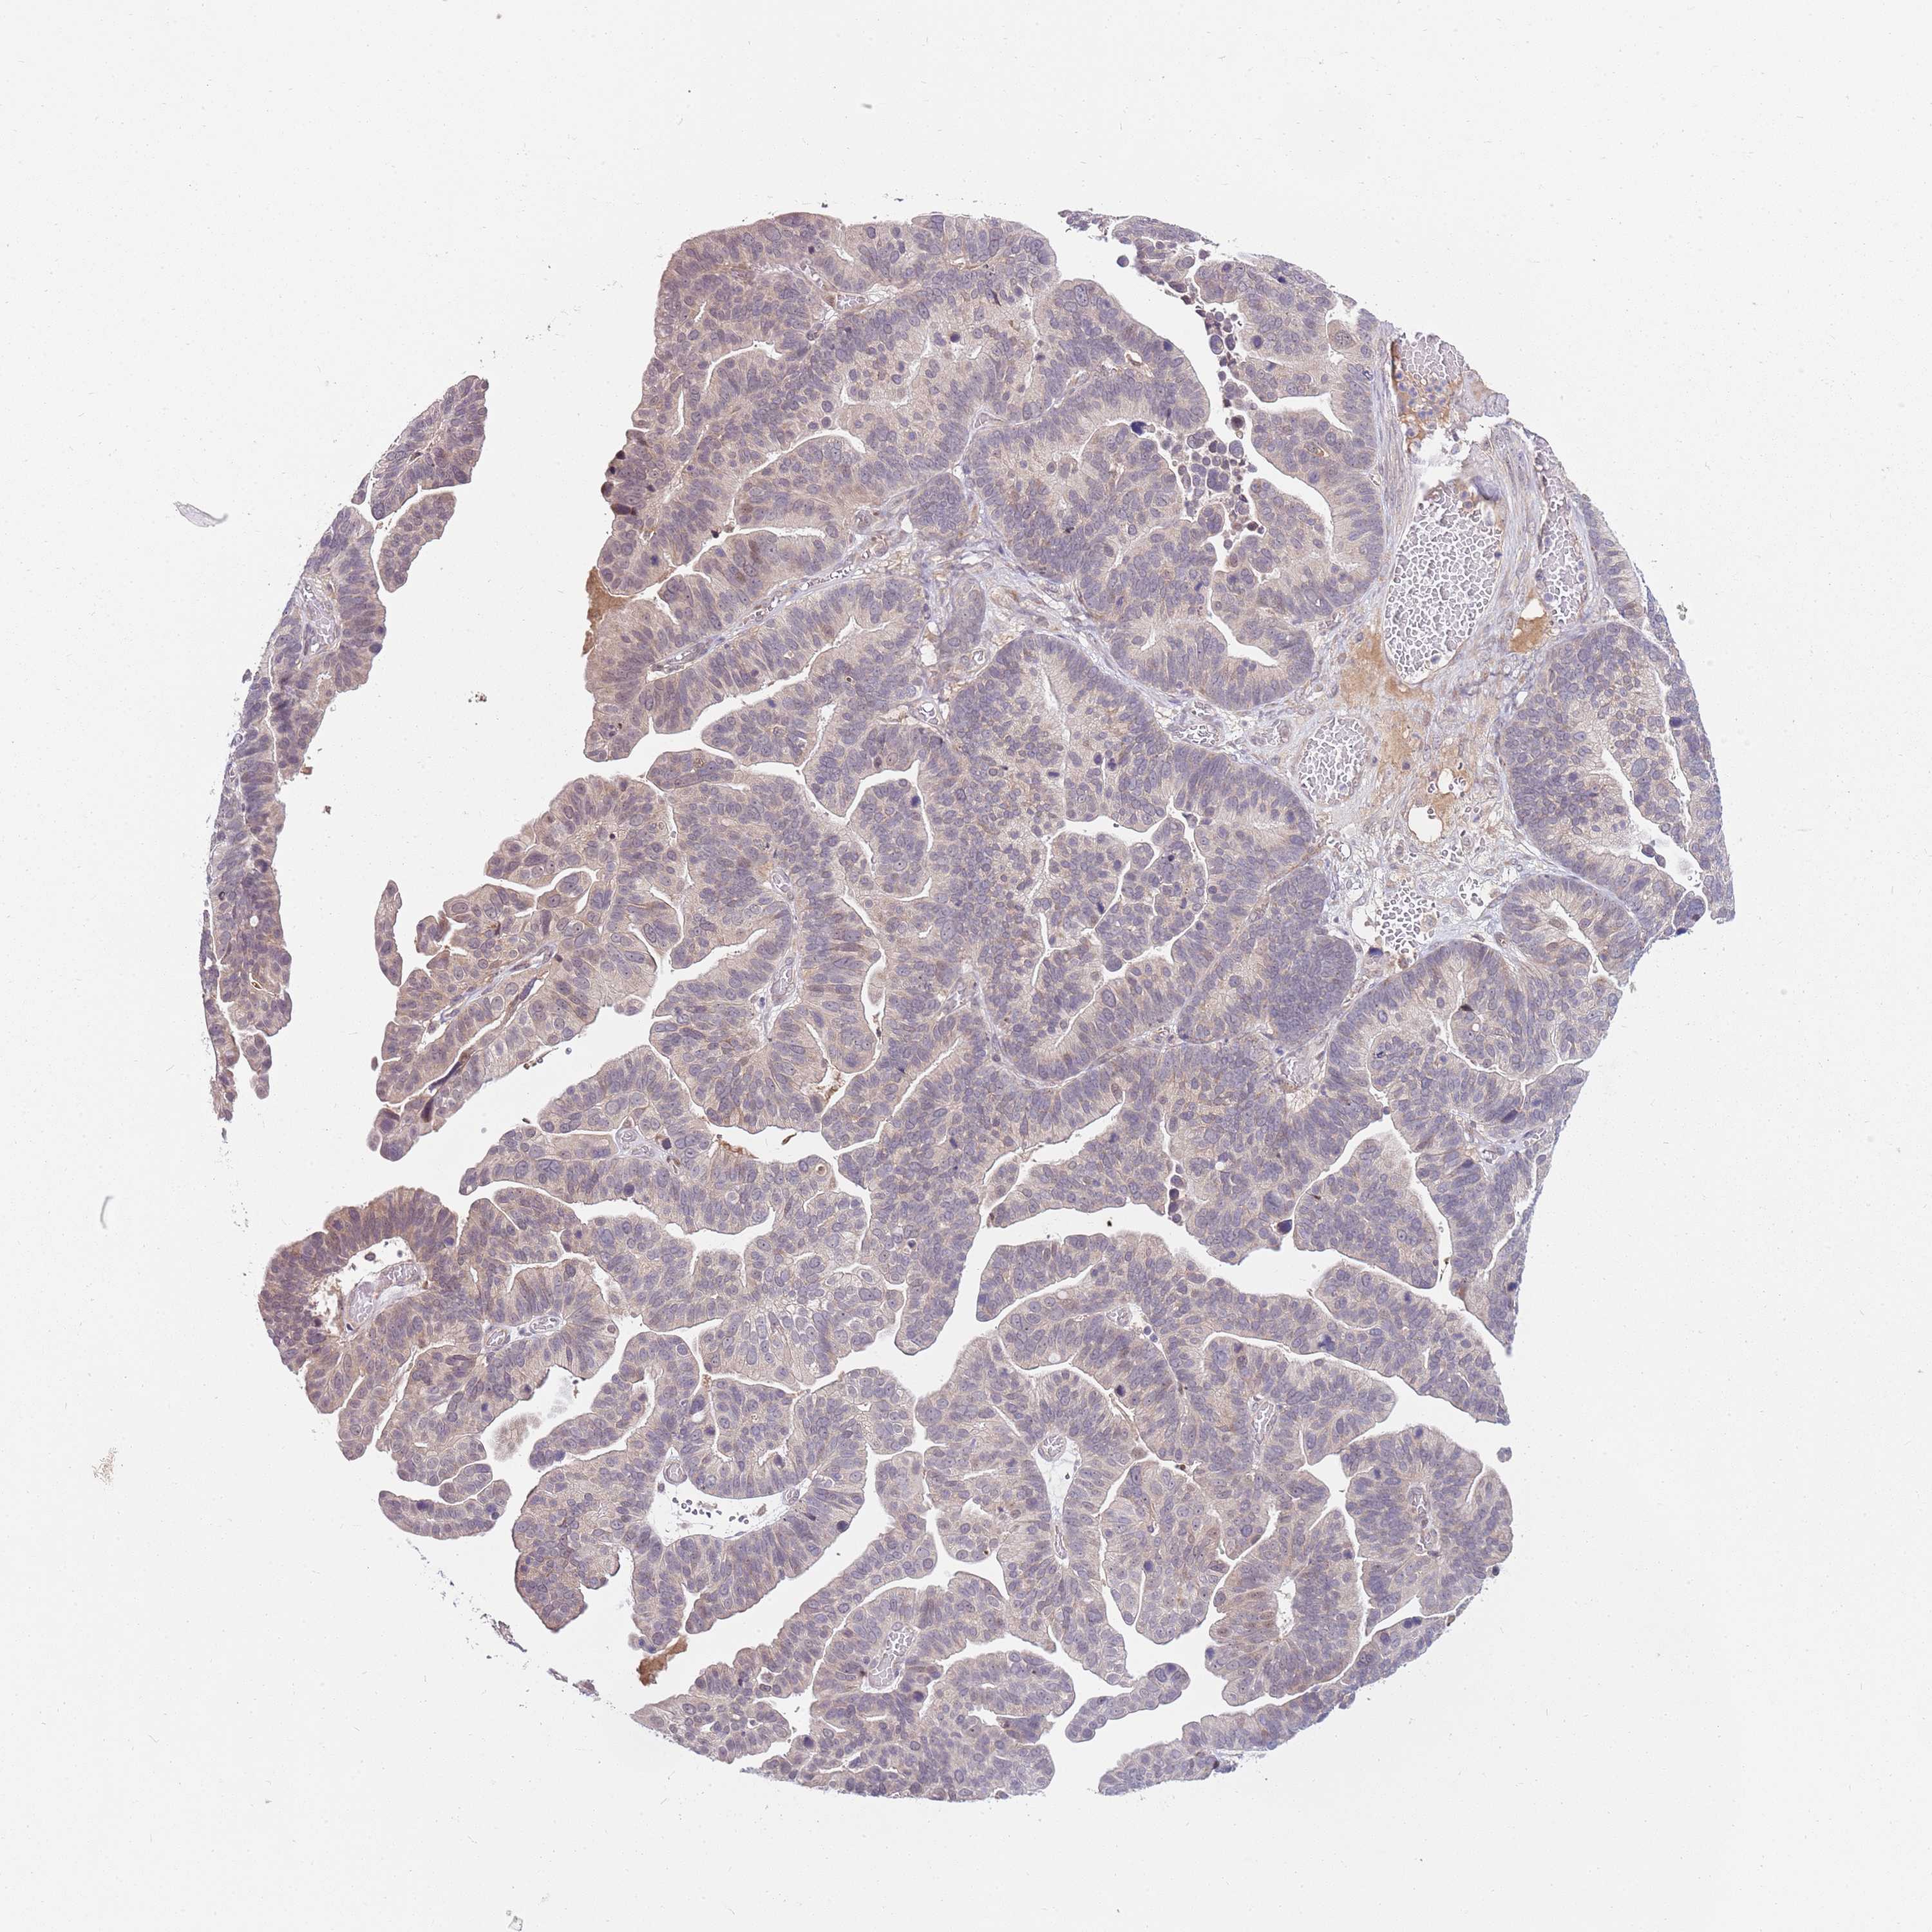

OVARIAN CANCER - Protein expressioni

A mouse-over function shows sample information and annotation data. Click on an image to view it in a full screen mode. Samples can be filtered based on level of antibody staining by selecting one or several of the following categories: high, medium, low and not detected. The assay and annotation is described here.

Note that samples used for immunohistochemistry by the Human Protein Atlas do not correspond to samples in the TCGA dataset.

Antibody stainingi

Antibody staining in the annotated cell types in the current human tissue is reported as not detected, low, medium, or high, based on conventional immunohistochemistry profiling in selected tissues. This score is based on the combination of the staining intensity and fraction of stained cells.

Each image is clickable and will lead to virtual microscopy that enables deeper exploration of all samples and also displays staining intensity scores, fraction scores and subcellular localization as well as patient and tissue information for each sample.

Antibody HPA047624

Antibody HPA054627

Staining

High

Medium

Low

Not detected

Intensity

Strong

Moderate

Weak

Negative

Quantity

>75%

75%-25%

<25%

None

Location

Nuclear

Cytoplasmic/membranous

Cytoplasmic/membranous,nuclear

Cystadenocarcinoma, serous, NOS

Carcinoma, NOS

Cystadenocarcinoma, mucinous, NOS

Carcinoma, endometroid